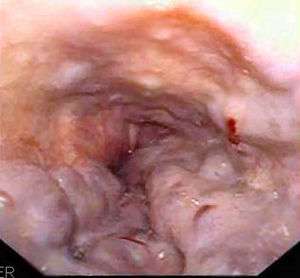

| Gastroscopy image of esophageal varices with prominent cherry-red spots | |

Esophageal varices are diagnosed with endoscopy.[2]

Dilated submucosal veins are the most prominent histologic feature of esophageal varices. The expansion of the submucosa leads to elevation of the mucosa above the surrounding tissue, which is apparent during endoscopy and is a key diagnostic feature. Evidence of recent variceal hemorrhage includes necrosis and ulceration of the mucosa. Evidence of past variceal hemorrhage includes inflammation and venous thrombosis.